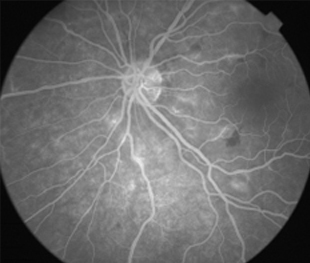

Angiografía OI

- Angiografía: teñido arterial, escape capilar, más tardíamente, no perfusion arteriolar y venular con teñido de las paredes vasculares y dilatación venosa.